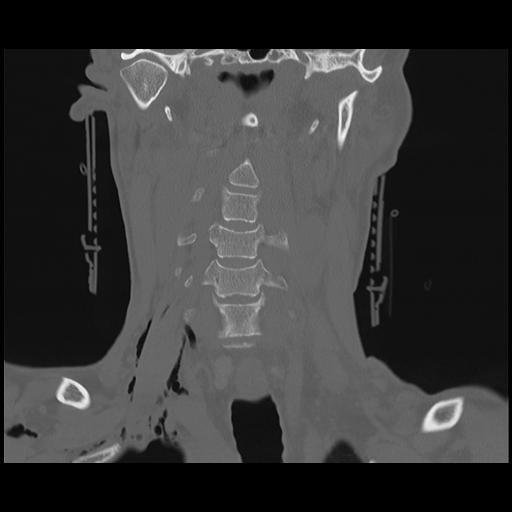

16 HUESO,,Coronal,2.000,HUESO,Coronal,